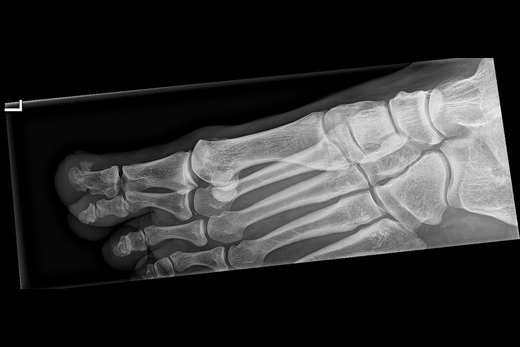

Patiënt A, een 12-jarige jongen, heeft sinds een jaar een zwelling onder de nagel van de rechter grote teen. Aanvankelijk denkt de huisarts aan verruca vulgaris, maar de huidafwijking verdwijnt niet na behandeling met vloeibare stikstof. Histologisch onderzoek wijst op een bloedblaar. De huisarts verwijst de patiënt naar de dermatoloog. Subunguaal aan de rechter grote teen is sprake van een onscherp begrensde, bruine -hyperkeratotische nodulus van 0,6 cm, die de nagelplaat omhoogdrukt. De laesie voelt hard aan. De klinische diagnose luidt digitale exostose [figuur 1]. De dermatoloog laat een röntgenfoto maken, waarop een subunguale exostose aan de tuft van de grote teen van de rechtervoet te zien is [figuur 2]. De patiënt krijgt een verwijzing naar de orthopedisch chirurg voor excisie. Histologisch zijn er geen aanwijzingen voor een maligniteit.

Figuur 1 | De grote teen van patiënt A met exostose zichtbaar distaal op de eindfalanx digitus 1.

De grote teen van patiënt A met exostose zichtbaar distaal op de eindfalanx digitus 1.